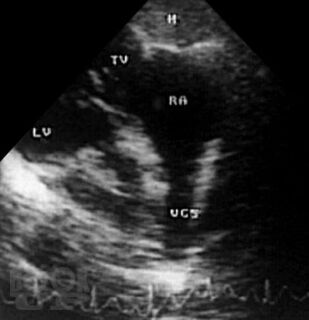

В атласе на большом числе богато иллюстрированных примеров дана эхо- и допплеркардиографическая картина врожденных пороков и ряда заболеваний сердца, а также правила применения методики ультразвукового исследования. Издание восполняет дефицит информации об ультразвуковой диагностике многих сложных врожденных пороков сердца и возможности оценки состояния больных после хирургической коррекции порока.

При подготовке атласа сотрудниками Научного центра сердечно-сосудистой хирургии им. А.Н. Бакулева РАМН (директор – академик РАМН Л.А. Бокерия) использован опыт ультразвукового исследования больных с пороками и заболеваниями сердца (более 60000 пациентов), обследованных в Центре за период с 1976 по 2003 г.